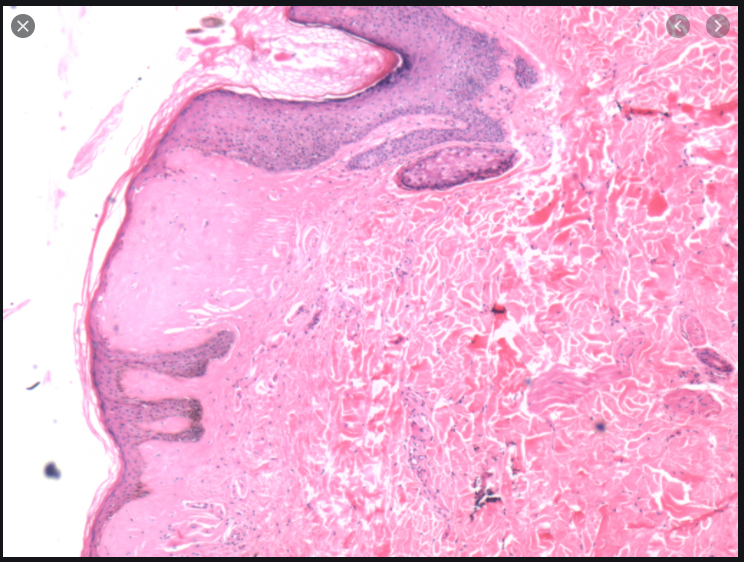

Relatively normal looking biopsy but diminished granular layer and compact hyperorthokeratosis

Ichthyosis Vulgaris

Normally if there is hyperkeratosis the granular layer will be thick or if there is parakeratosis the granular layer will be absent. In this there will be hyperkeratosis without a granular layer which is odd.